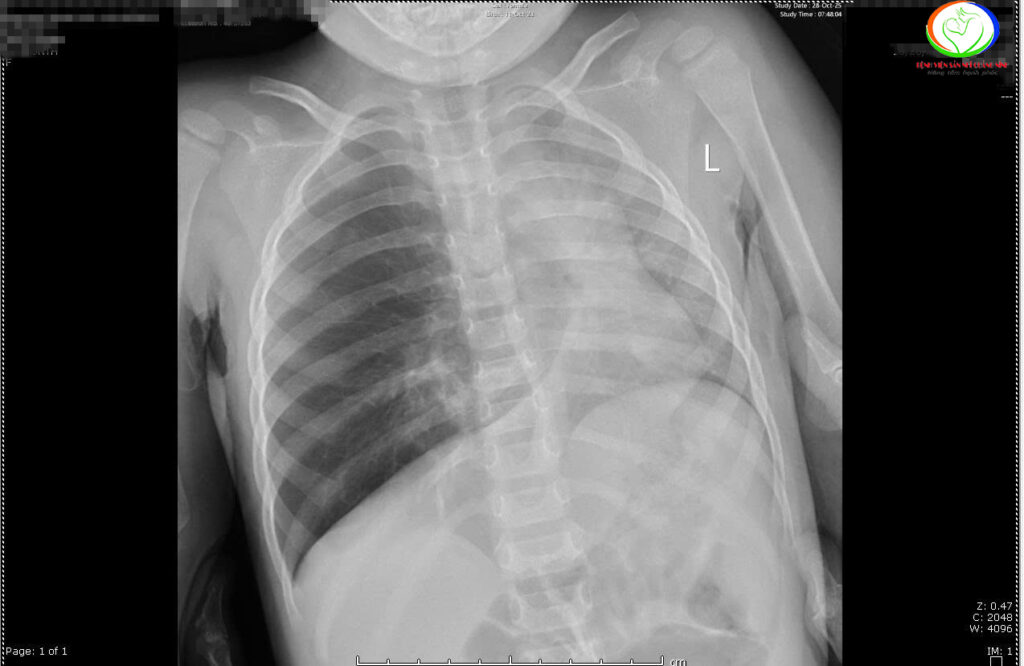

Nội soi khí phế quản phổi gắp dị vật đường thở nguy hiểm cho bệnh nhi 25 tháng tuổi và 29 tháng tuổi tại Bệnh viện Sản Nhi tỉnh Quảng Ninh

Bệnh viện Sản Nhi Quảng Ninh mới đây tiếp nhận một số trường hợp là bé Đ. M. A (29 tháng tuổi), thường trú tại xã Khoái Châu, tỉnh Hưng Yên và bé N.N.L (25 tháng tuổi), trú tại Phường Hà Lầm, tỉnh Quảng Ninh phải nhập viện điều trị vì hóc dị vật nguy […]